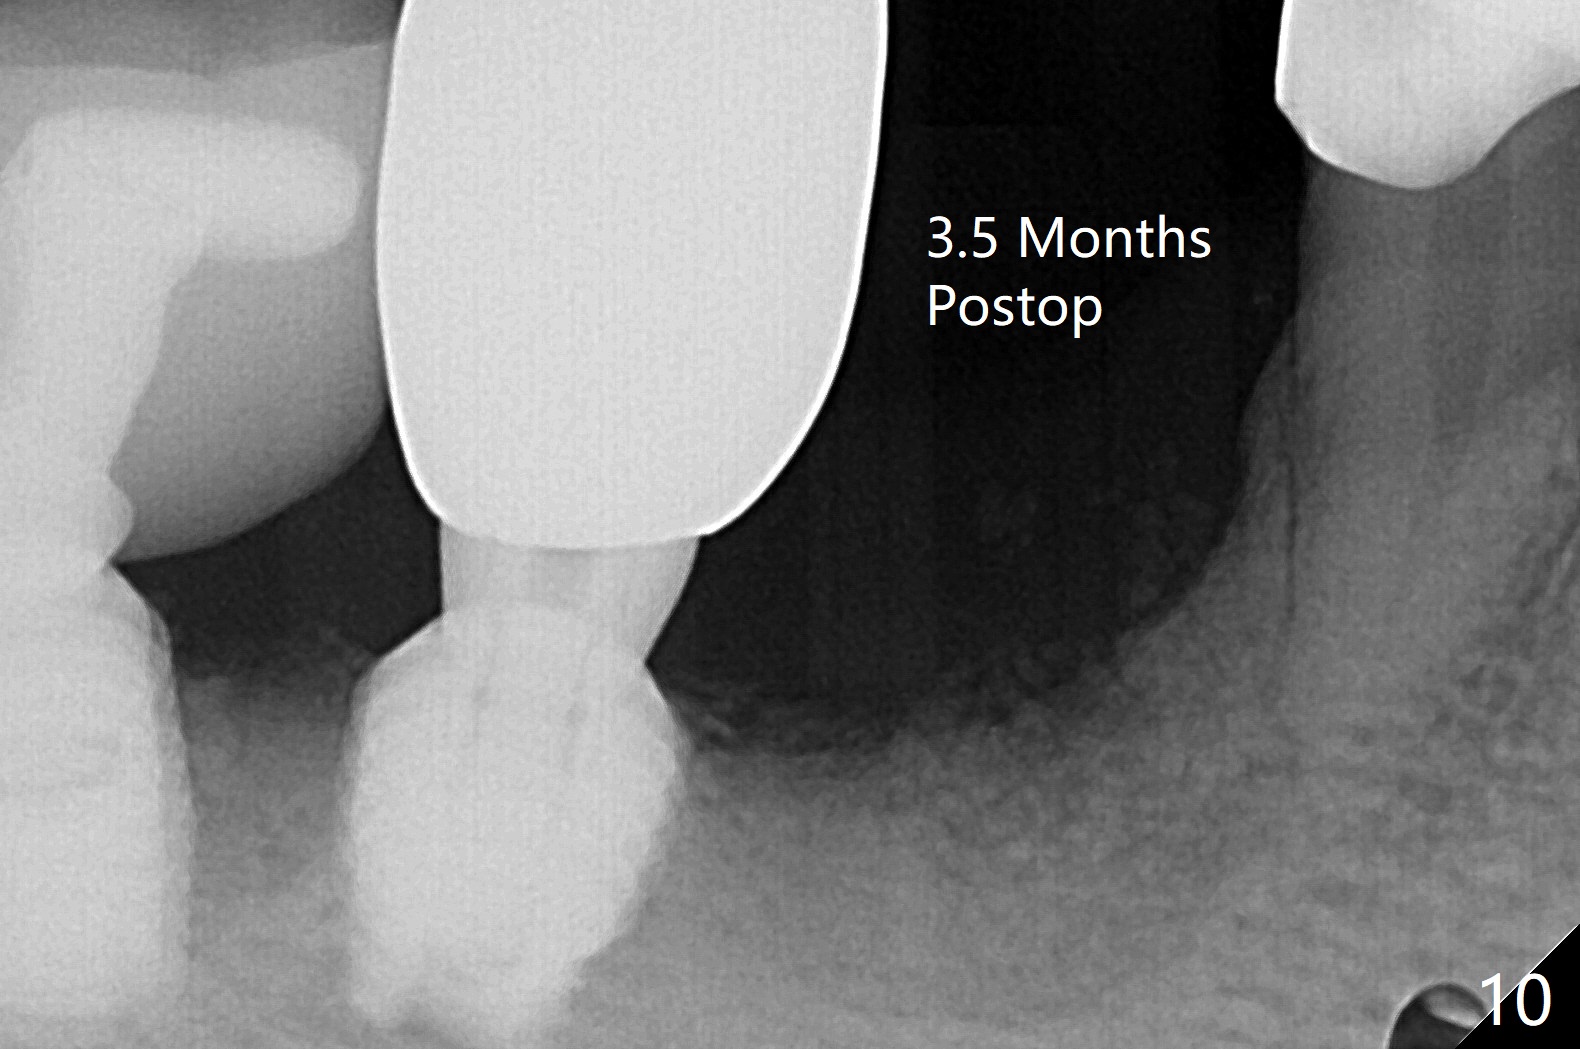

52岁男右下4植体脱落三天回到诊所(图一),植牙创尚未闭锁,顺着开口去除肉芽组织,冲洗,充填皮质骨骨粉(图二,三),颊侧骨板外形恢复(图四,五:*)。重新植入UF植体(5)颊侧还有薄颊侧骨板(图五:>),而6植体周围骨质吸收(图六),植骨好像有希望,植体还在牙槽骨范围,也有利于5植体生存。术后12天伤口愈合(图七)。尽管使用水枪,仍有6植体周围炎,需要治疗(图八)。由于右侧手术,病人不得不用左侧咀嚼,他认为左下4松动,无法挽救。术后3.5个月牙槽嵴和角化龈缩小(图九),需要切开使用导板。术后3.5个月骨粉高度明显下降(图十)。只能植入4x8.5毫米植体(图十一)。